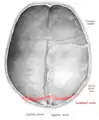

درز لامی (انگلیسی: Lambdoid suture) بین استخوانهای آهیانه و پسسری واقع شده است.

![]() Lambdoid suture (labeled at bottom right) | |

با اتصال Asterion دو طرف به هم طوری که از Lambda بگذرد، مسیر آن به دست میآید.